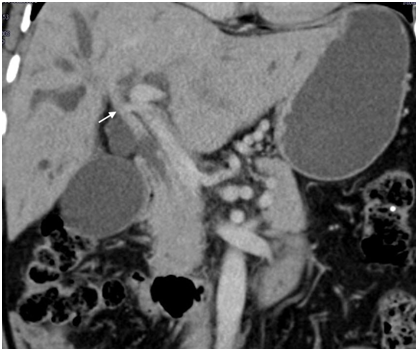

Figure 3 Type IIIa well differentiated hilar cholangiocarcinoma treated with right hepatectomy - Coronal CT image reveals tumor mass in common hepatic duct (white arrow) extending to right hepatic duct (black arrow).